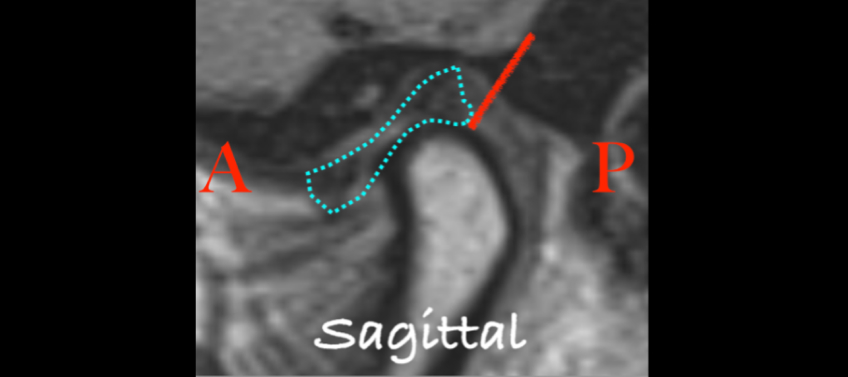

A Class II mandibular shift in a growing patient may indicate a structural change in the TM joints. The normal anatomy places the articular disk on top of the condyle, with the posterior band at the 1 o’clock position (Fig. 3). When the disk is displaced anteriorly, the risk of early cessation of vertical condylar growth increases. Recognizing signs of temporomandibular joint changes helps both dentist and patient understand the risks of damage to the dentition or restorations caused by the Class II mandibular shift. A loss of vertical dimension in the TM joints often causes the first contact point to shift to the most distal teeth.

The articular disk is a biconcave structure that’s thicker on the anterior and posterior aspects, with a thinner avascular central bearing zone. The central bearing zone is typically 2–3 mm thick and functions to distribute the load between the condyle and the glenoid fossa. When the disk is properly positioned, the posterior band wraps around the back side of the condyle, positioning it in a concentric location (Fig. 4a). When a disk herniates, it can cause a deflection of the condyle, disrupting the joint space and providing insight into the disk’s position (Fig. 4b).